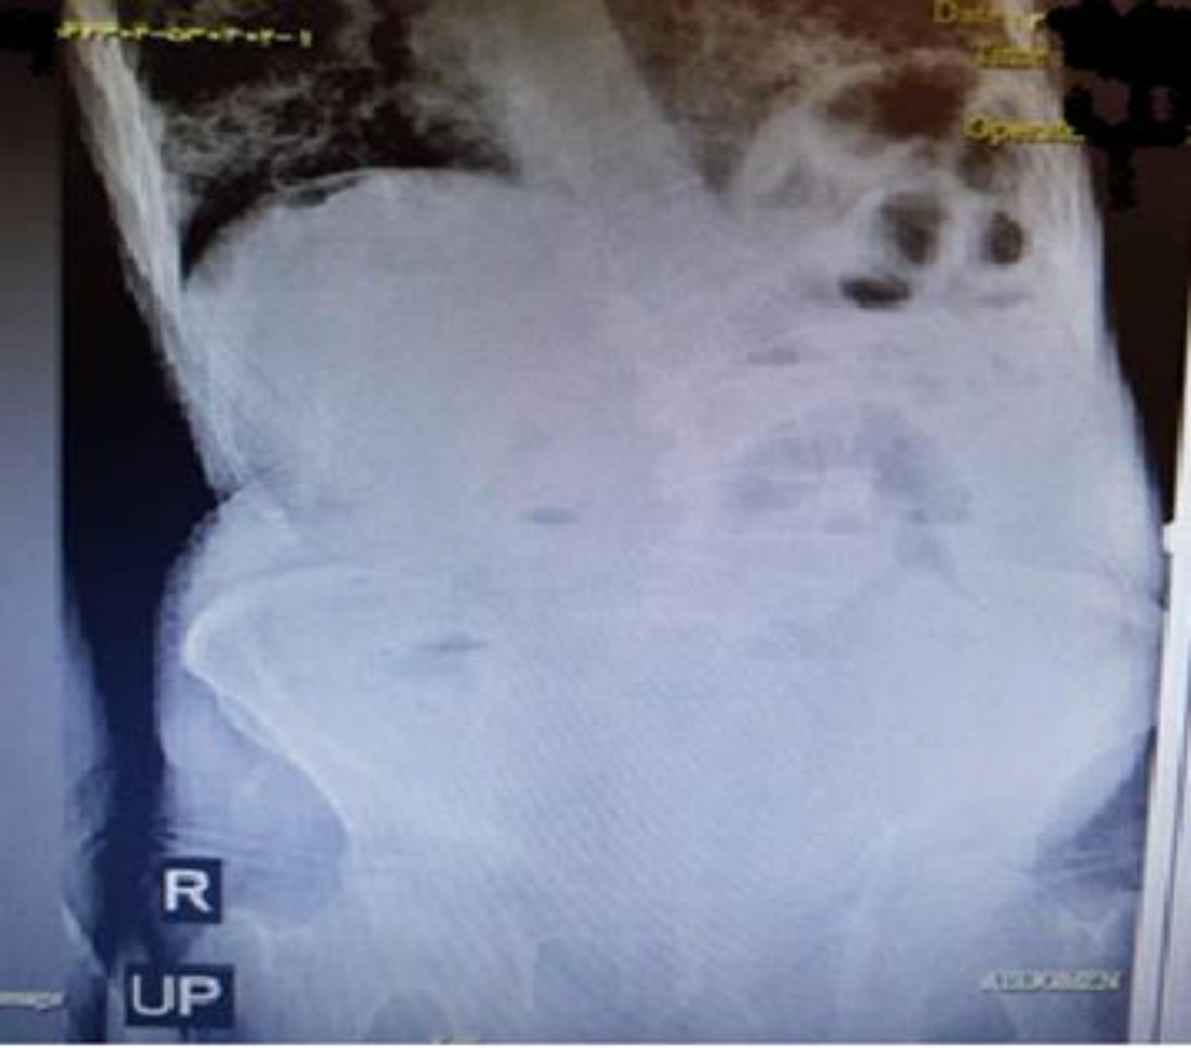

An 88-year-old man with a diagnosis of COVID-19 confirmed by PCR was referred to the emergency department due to respiratory distress from one week ago and melena (several times) from three days ago, abdominal pain, bloating, and inability to expel gas and excrete feces. During the abdominal examination, he had generalized tenderness, rebound tenderness, and abdominal distention. He had anemia and low hemoglobin and hematocrit, and the levels of urea and creatinine were high. Considering abdominal exami-nation and final assessment (Figure 7), a diagnosis of peritonitis was made. Accordingly, the patient was prepared for emergency surgery; during the operation, about 130 cm of the ileum was resected due to necrosis. Unfortunately, two days after surgery, the patient died due to respiratory arrest.

Fig. 7.Abdominal X-ray, upright and supine